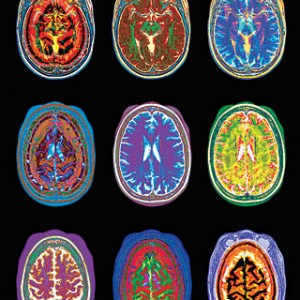

So they don’t become depressed or manic,

a mostly neutral pH they’ll maintain,

otherwise they might stroke-out or panic

and, by this measure,

we might call them sane,

yet, simply gauged by electrical spike,

we find few two likely to think alike.